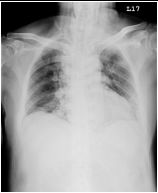

7.CC: cough for one year and back pain